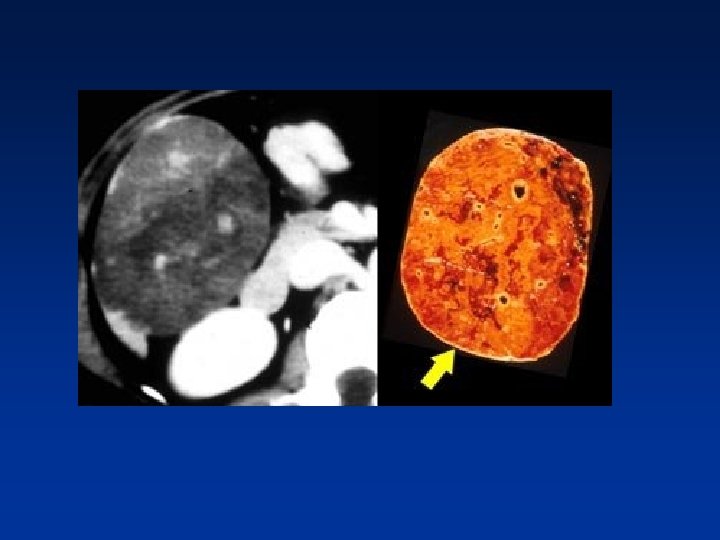

• Any hypervascular lesion in a cirrhotic liver is hepatocellular carcinoma untill proven otherwise. • HCC may be solitary, multifocal or diffusely infiltrating. • Large HCC typically have a mosaic appearance due to hemorrhage & fibrosis.

• HCC is a silent tumor, so if patients don’t have cirrhosis or hepatitis C , you will discover them in a late stage. • They tend to be large with mozaic pattern , a capsule , hemorrhage and necrosis. • HCC become isodense or hypodense to liver in the portal venous phase due to fast wash-out • On delayed images, the capsule and sometimes septa demonstrate prolonged enhancement.

• Large HCC with mozaic pattern in a non cirrhotic liver